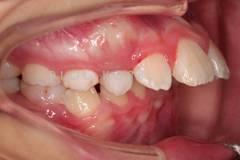

下面這個(gè)小患者就存在需早期矯正的問題。通過早期矯正,在不長(zhǎng)的時(shí)間內(nèi)就達(dá)到極為明顯的療效。她的情況如果等到牙齒替換完畢后再解決,矯治的難度則會(huì)非常大。

早期矯正之前